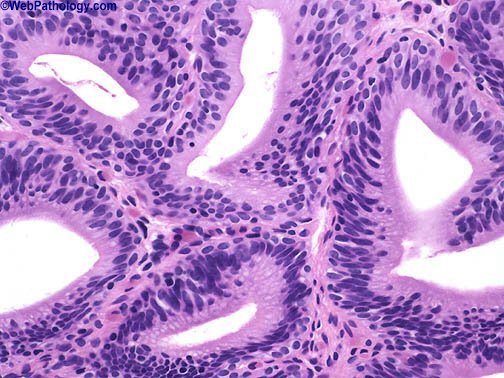

This biopsy suggests a diagnosis of ___, putting this patient at an increased risk of ____.

Cystitis glandularis/cystica

Adenocarcinoma of bladder

(Look for clear spaces lined by cuboidal or urothelial epithelium)